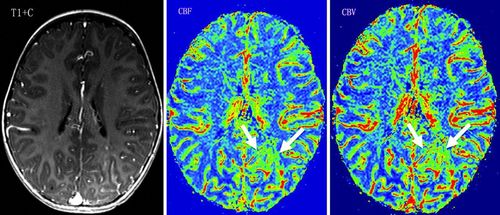

- Nhồi máu não giai đoạn tối cấp tính: chụp cộng hưởng từ cho phép chẩn đoán sớm hơn chụp cắt lớp vi tính các nhồi máu não. Chụp mạch máu não phối hợp với chụp tưới máu não (perfusion) cho phép chẩn đoán rất sớm nhồi máu não tối cấp, phát hiện mạch máu bị tắc, hẹp để can thiệp kịp thời cho bệnh nhân.

- U não: Khảo sát tưới máu khối u và các mạch máu nuôi u.